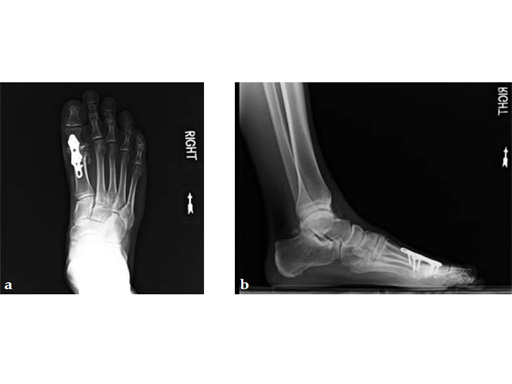

Case 4: First TMT fusion plate

A 60-year-old woman with pes plano abductovalgus (flatfoot deformity).

Case provided by Andrew Sands, New York, New York, USA

The patient was treated by headless compression screw 6.5 tuber osteotomy, TMT plantarflexing osteotomy, and first TMT fusion a plate.